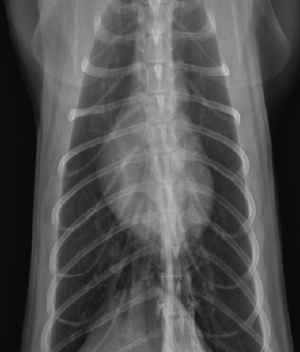

• 흉부 방사선

• 마취 유지 시 가장 중요한 심장, 폐 등의 이상을 파악하기 위해 흉부 방사선 검사가 필요합니다.